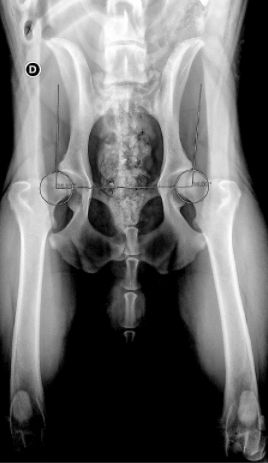

Le dépistage de la dysplasie repose tout d’abord sur un examen clinique spécialisé vigile puis sous sédation. La réalisation de radiologies règlementaires sont effectuées sous anesthésie générale tout comme la mesure d’angle (Norberg Olson) ainsi que la mesure du signe d’Ortolani (permet un examen des 2 hanches simultanément) . Enfin, l’on mesure l’indice de distraction qui va donner un index de distraction soit un ratio compris entre 0 et 1 qui quantifie le déplacement latéral de la tête du fémur.

Le diagnostic de dysplasie de la hanche ne repose en aucun cas sur une seule radiographie et fait appel à des compétences orthopédiques.